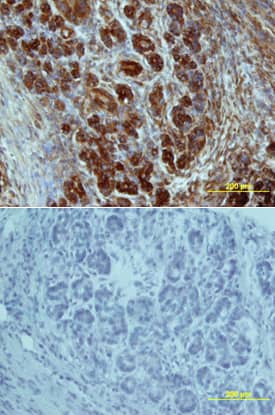

Glut2 in Human Pancreatic Cancer Tissue.

Glut2 was detected in immersion fixed paraffin-embedded sections of human pancreatic cancer tissue using Mouse Anti-Human Glut2 Monoclonal Antibody (Catalog # MAB1414) at 5 µg/mL overnight at 4 °C. Tissue was stained using the Anti-Mouse HRP-DAB Cell & Tissue Staining Kit (brown; Catalog # CTS002) and counterstained with hematoxylin (blue). Specific labeling was localized to the plasma membrane of exocrine cells. View our protocol for Chromogenic IHC Staining of Paraffin-embedded Tissue Sections.

Glut2 antibody in Human Pancreas by Immunohistochemistry (IHC-P).

Glut2 in Human Pancreas.

Glut2 was detected in immersion fixed paraffin-embedded sections of human pancreas array using Mouse Anti-Human Glut2 Monoclonal Antibody (Catalog # MAB1414) at 25 µg/mL overnight at 4 °C. Tissue was stained using the Anti-Mouse HRP-DAB Cell & Tissue Staining Kit (brown; Catalog # CTS002) and counterstained with hematoxylin (blue). Lower panel shows a lack of labeling if primary antibodies are omitted and tissue is stained only with secondary antibody followed by incubation with detection reagents. View our protocol for Chromogenic IHC Staining of Paraffin-embedded Tissue Sections.